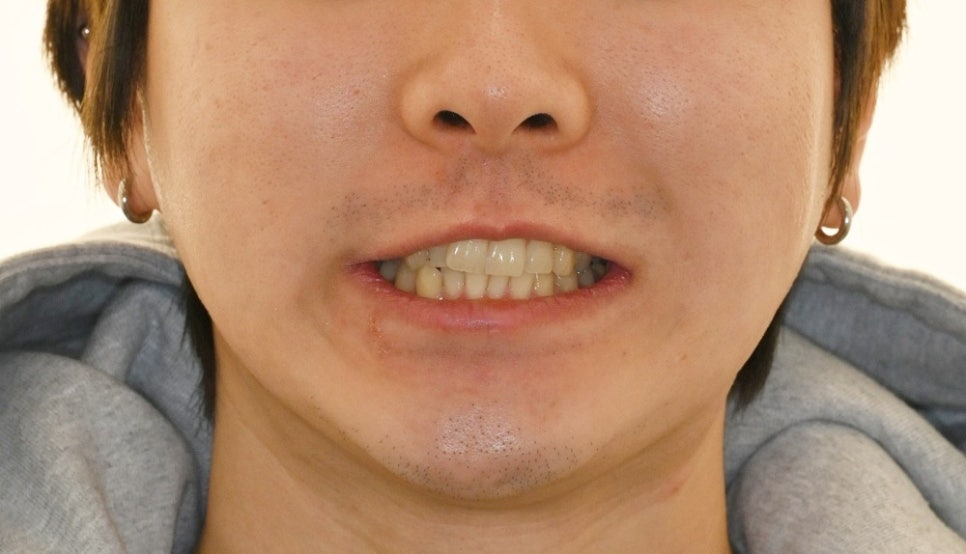

검사 당시 정면 얼굴 사진에서는

턱 끝이 우측으로 편위 되어 있었고,

웃을 때 입술 비대칭도 관찰되었습니다.

위턱 중심선은

얼굴 중심에서 오른쪽으로 벗어나 있었으며,

촬영일 : 23.12.04

위턱 치열도 오른쪽으로

기울어진 모습이었습니다.

시간이 지나며 치열이 가지런해지고,

웃을 때 입술 비대칭도 점차 완화되었습니다.